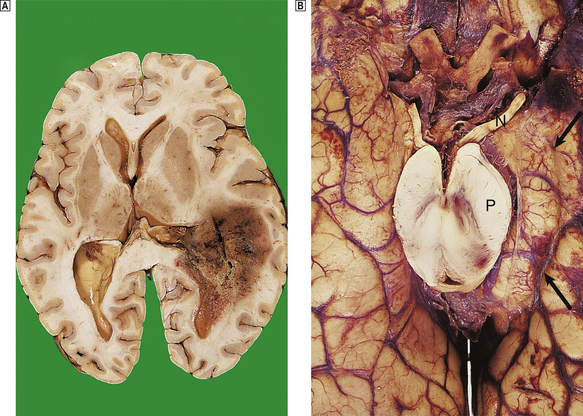

Herniations occur at several characteristic sites within the cranial cavity, depending on the site of the space-occupying lesion (Fig. 26.5). Transtentorial herniation is frequently fatal because of secondary haemorrhage into the brainstem (Fig. 26.6). This is a common mode of death in patients with large intrinsic neoplasms or intracranial haemorrhage.

image

Fig. 26.6 Herniation effects in the brain. image A large haemorrhagic neoplasm (glioblastoma) is present in the right cerebral hemisphere, causing shift of the midline structures to the left and compression of the right lateral ventricle. image Transtentorial herniation at the base of the brain. A prominent groove surrounds the displaced parahippocampal gyrus (arrow). The adjacent 3rd nerve (N) is compressed and distorted and the ipsilateral cerebral peduncle (P) is distorted with small areas of haemorrhage.